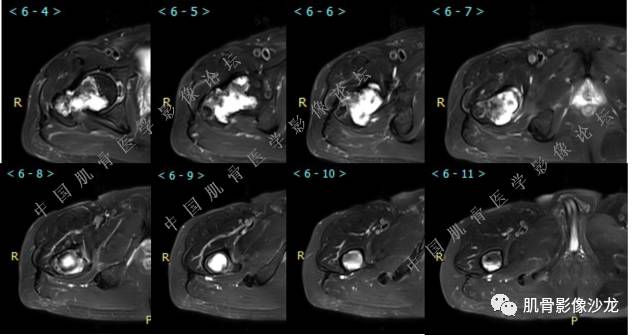

主诉:右大腿疼痛、活动受限20天

现病史:患者于20天前无明显诱因出现右下肢疼痛,活动受限,疼痛呈阵发性,活动后加重。自行口服止痛药芬必得,效果不佳,至当地医院治疗,检查发现右侧股骨近端病变。遂来诊

葛英霖 20:30 原发或继发动脉瘤样骨囊肿,继发于巨细胞瘤,软骨母,纤维组织细胞瘤,骨母等等

向以四 20:30 软骨母合并ABC,

Echo 20:30 我感觉本例硬化边不明显

医影在线 20:30 软骨母,/继发ABC

飞鹰行动 20:31 T2信号高,有软骨成分

Echo 20:32 T2确实有一块区域很亮 ,并有野液平

飞鹰行动 20:33 有侵袭性

飞鹰行动 20:35 骨皮质破坏,周围骨质异常信号

葛英霖 20:36 这不是良性病变

葛英霖 20:36 中间型可能性极大

葛英霖 20:37 明显侵蚀骨内膜啊,硬化边也不完整 (细箭头所示)

葛英霖 20:43 提不提也很明显继发了abc

Echo 20:44 葛老师~继发ABC是根据有液液平面判断么?

葛英霖 20:44 是

葛英霖 20:45 abc就是出血来的

葛英霖 20:46 明显的多囊状改变,液液平面

葛英霖 20:47 可以,没有液液平面也不妨碍考虑